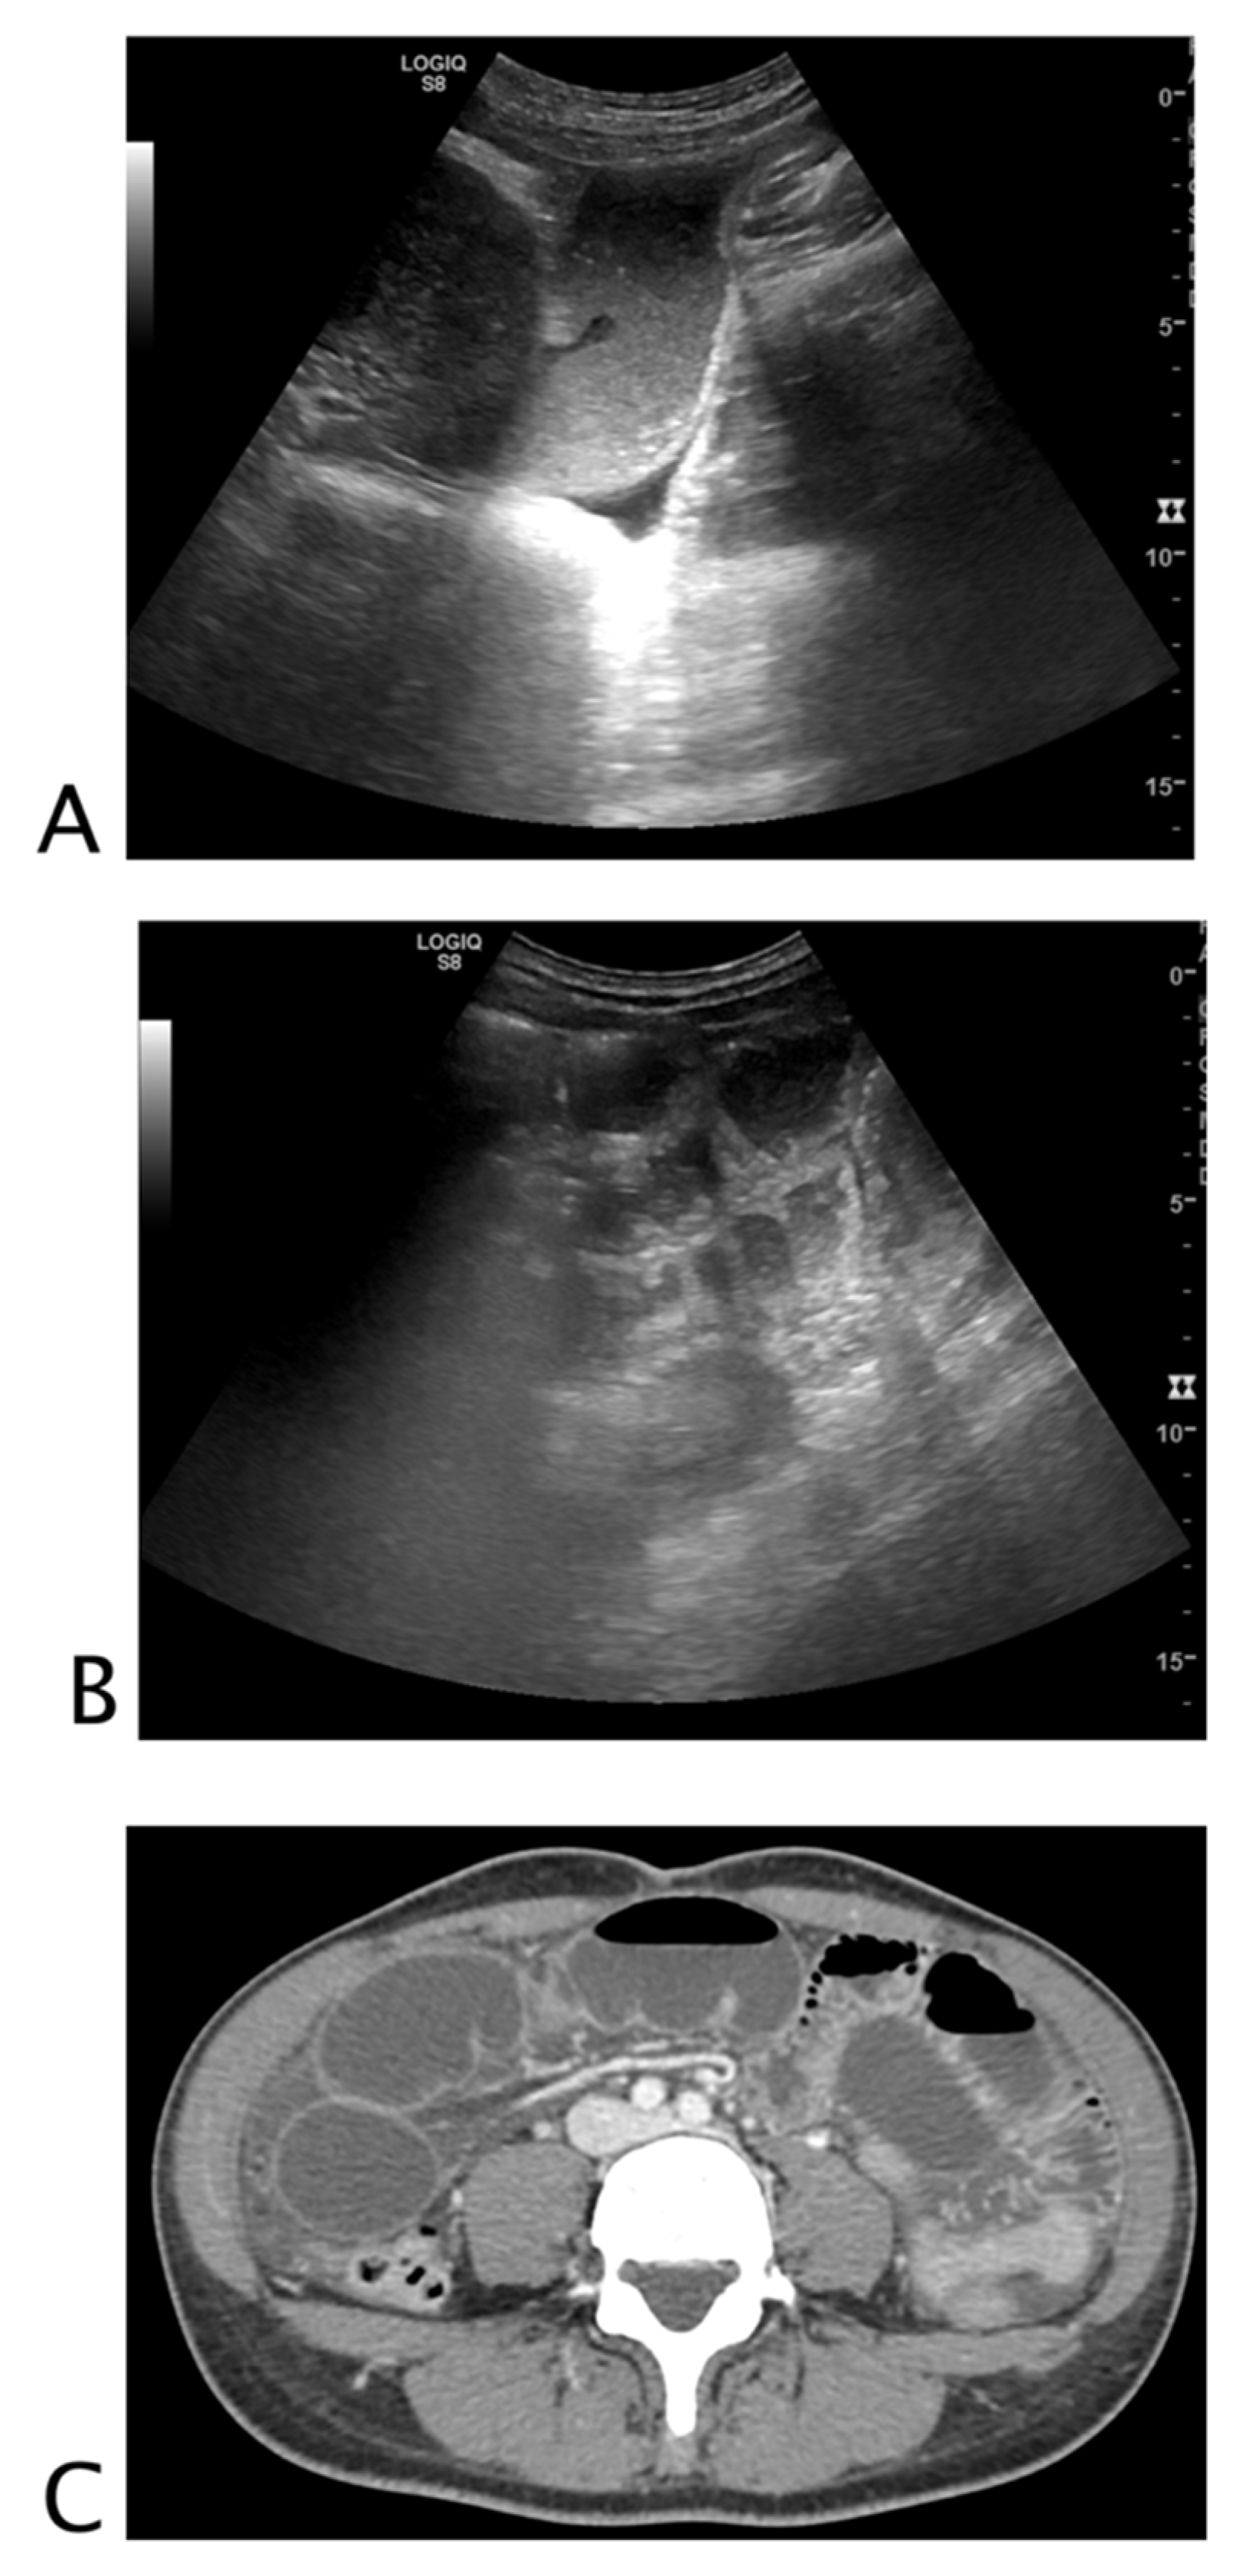

2.1. Looking for Black Where It Should Not Be

2.1.1. Non-Traumatic Hemoperitoneum

2.1.2. Non-Traumatic Free Fluid

2.1.3. Post-Surgical Complications